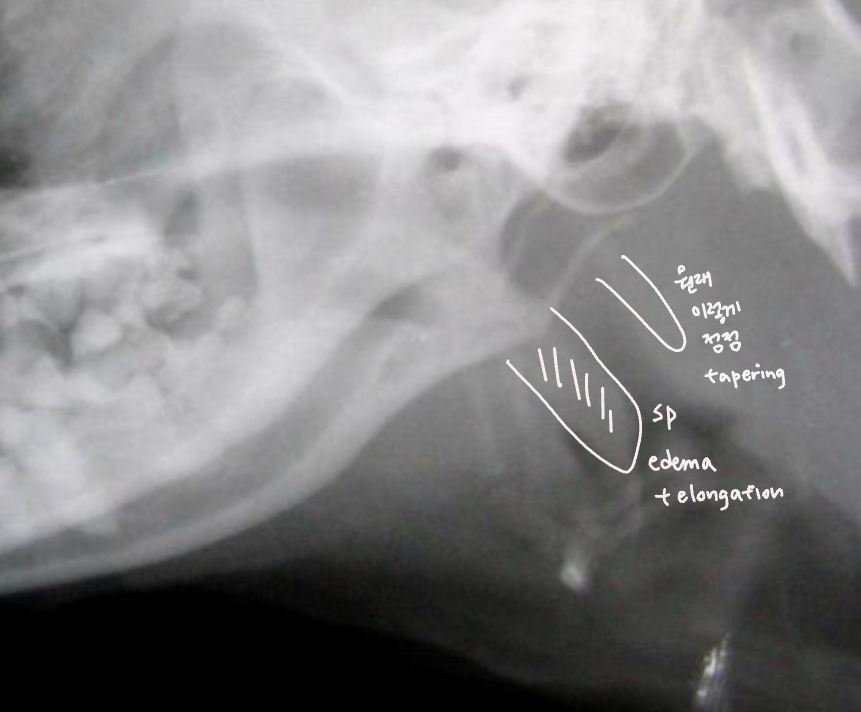

- soft palate edema & elongation (연구개노장)

- laryngeal edema, saccules, collapase, paralysis